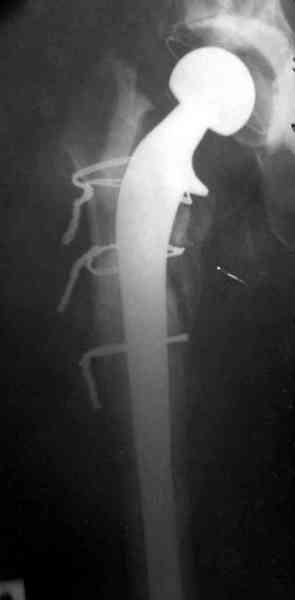

Приглашенный хирург установил ревизионный вариант бедренного компонента без замены ацетабулярного компонента, что осложнилось нагноением и свищами на уровне сустава и средней трети бедра. После двухгодичного безуспешного лечения перевязками и антибиотиками больная обратилась к нам на консультацию.

Для спейсера в бедро использовал старый длинный бедренний компонент меньшего диаметра, облепленный со всех сторон цементом с антибиотиком.

№3-6 снимки с осложнением